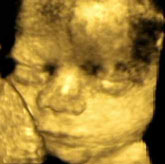

Intre metodele moderne de depistare a acestui tip de malformatii se afla ultrasonografia, care da posibilitatea vizualizarii inainte de nastere a principalelor malformatii usoare sau majore, a explicat prof. dr. Vladareanu. El a adaugat ca acest lucru da posibilitatea luarii unor decizii in cazul unor sarcini cu probleme.

In prezent, exista aparatura de ultrasonografie foarte performanta, dar si foarte scumpa. Cu tehnicile actuale pot fi vizualizate aproape toate anomaliile de structura, cele metabolice, enzimatice, insa nu pot fi depistate prin aceste tehnici anomaliile morfologice si cele enzimatice, a subliniat specialistul.

Intre anomaliile cele mai frecvente se numara cele cardiace, unde diagnosticarea se poate face inca din primul trimestru de sarcina, iar in cazul unor malformatii majore se pot lua masuri de intrerupere a sarcinii. Alt tip de malformatie frecventa si care poate fi depistata prin aceasta tehnica este defectul de tub neural de inchidere de coloana (spida biffida).